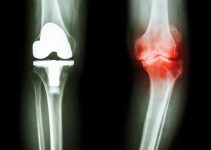

Протезирование позвонков. Если позвонок не подлежит реконструкции, его можно заменить, установив на его место протез. Этот метод позволяет восстановить свободу движений в полном объеме, без ограничений.